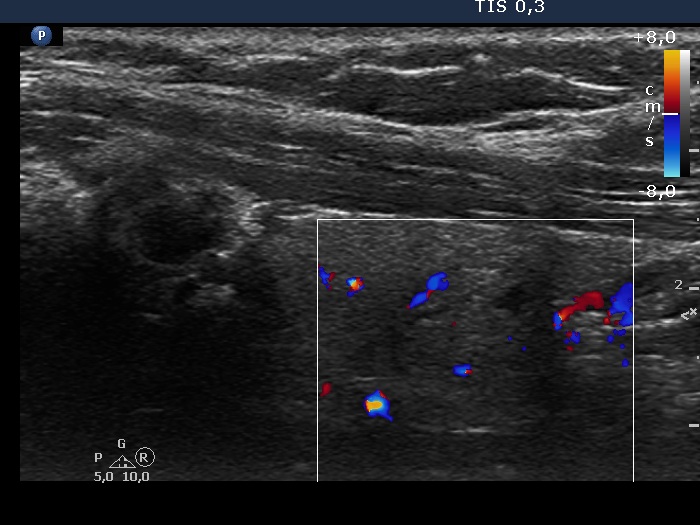

Study on 100 consecutive patients with thyroid nodule - case 004 (ultrasonographic picture 7)

Lower part of the lobe, transverse scan, color Doppler mode. The lesion presents signs of perinodular bood flow.